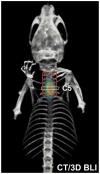

Neural stem cells (NSCs) are being investigated as a possible treatment for amyotrophic lateral sclerosis (ALS) through intraspinal transplantation, but no longitudinal imaging studies exist that describe the survival of engrafted cells over time. Allogeneic firefly luciferase-expressing murine NSCs (Luc+-NSCs) were transplanted bilaterally (100,000 cells/2μl) into the cervical spinal cord (C5) parenchyma of pre-symptomatic (63day-old) SOD1G93A ALS mice (n=14) and wild-type age-matched littermates (n=14). Six control SOD1G93A ALS mice were injected with saline. Mice were immunosuppressed using a combination of tacrolimus+sirolimus (1mg/kg each, i.p.) daily. Compared to saline-injected SOD1G93A ALS control mice, a transient improvement (p<0.05) in motor performance (rotarod test) was observed after NSC transplantation only at the early disease stage (weeks 2 and 3 post-transplantation). Compared to day one post-transplantation, there was a significant decline in bioluminescent imaging (BLI) signal in SOD1G93A ALS mice at the time of disease onset (71.7±17.9% at 4weeks post-transplantation, p<0.05), with a complete loss of BLI signal at endpoint (120day-old mice). In contrast, BLI signal intensity was observed in wild-type littermates throughout the entire study period, with only a 41.4±8.7% decline at the endpoint. In SOD1G93A ALS mice, poor cell survival was accompanied by accumulation of mature macrophages and the presence of astrogliosis and microgliosis. We conclude that the disease progression adversely affects the survival of engrafted murine Luc+-NSCs in SOD1G93A ALS mice as a result of the hostile ALS spinal cord microenvironment, further emphasizing the challenges that face successful cell therapy of ALS.